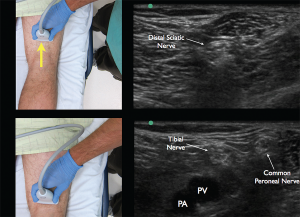

Figure 5. Appropriate movement of the ultrasound probe cephalad to visualize the joining of the tibial nerve with the common peroneal nerve forming the distal sciatic nerve. Note the common peroneal nerve approaching from the lateral aspect.